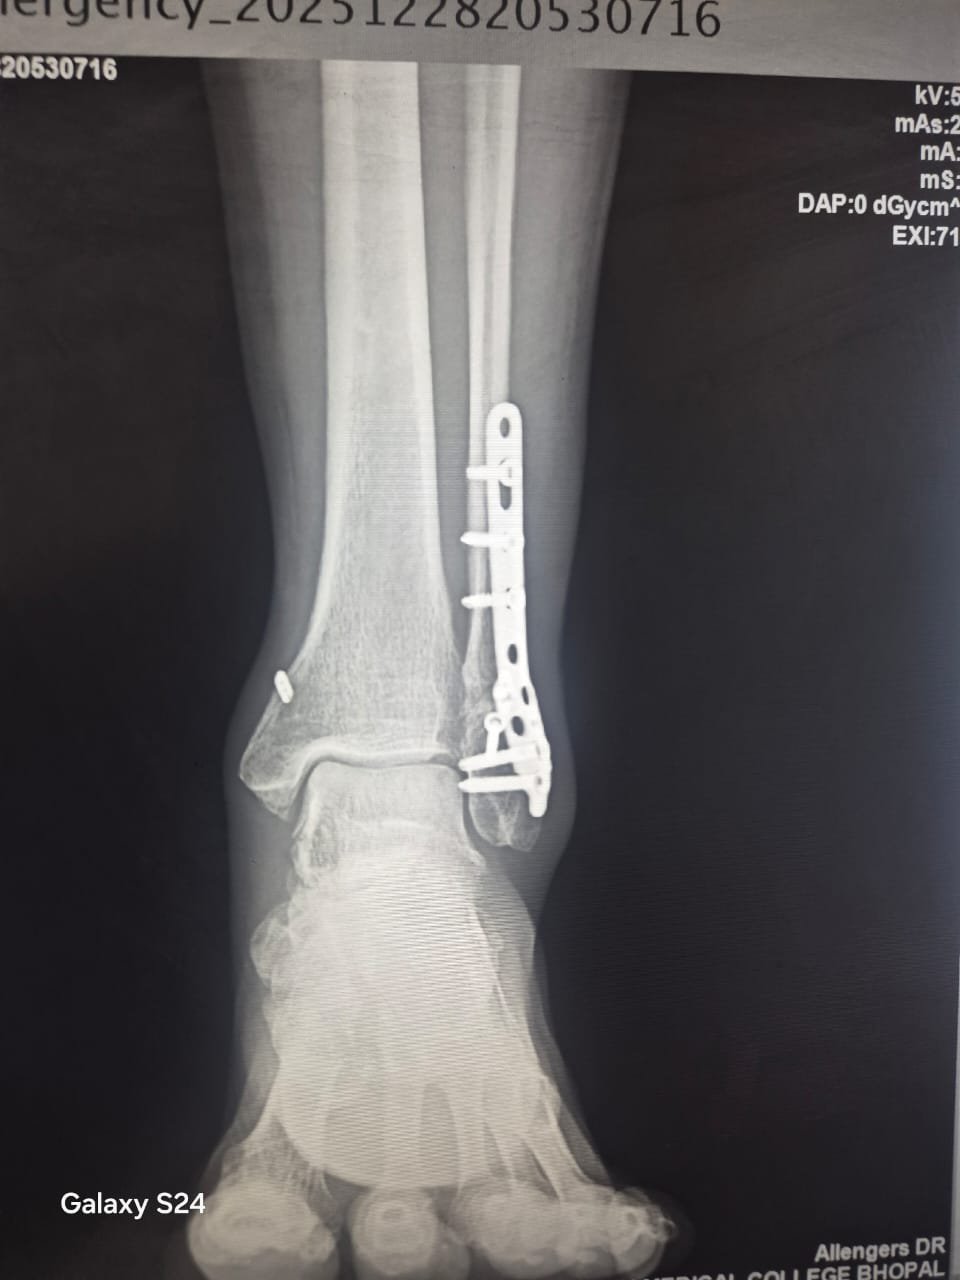

Orthopaedic Surgeon | Arthroscopy & Joint Replacement Specialist

Dr. Aditya Tripathi is a dedicated and skilled Orthopaedic Surgeon specializing in sports injuries, arthroscopy, and joint care. Known for his clinical precision, ethical practice, and patient-first approach, he focuses on helping patients regain mobility, strength, and confidence through evidence-based orthopaedic treatment. His academic background and hands-on clinical training reflect a strong foundation and a commitment to excellence in orthopaedic care.

Dr. Aditya Tripathi is widely appreciated by patients for his clear communication, honest medical guidance, and personalized treatment approach. His expertise in managing ACL tears, ligament injuries, shoulder conditions, and sports-related injuries makes him a trusted choice for comprehensive orthopaedic and sports injury care. Patients value his attention to detail, compassionate care, and focus on long-term recovery—establishing him as a reliable and respected orthopaedic specialist.

Specialization And Expertise

- Fracture Treatment